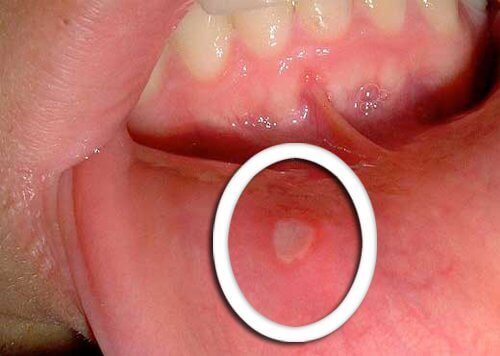

In de meeste gevallen ontwikkelt mondkanker zich in de carcinomen. Carcinomen zijn een specifieke celsoort, in de vorm van kleine platte rondjes. Het zijn niet gewoon blaasjes.

Het is normaal dat mensen met een lager immuunsysteem en mensen die vaak last hebben van orale infecties, blaasjes in de mond of aften hebben, de symptomen van deze ziekte niet meteen herkennen.

- De eerste symptomen van mondkanker zijn kleine blaasjes die maar niet genezen.

- Het is ook typisch dat een rode of witte kleur verschijnt op de tong, het tandvlees of de lippen.